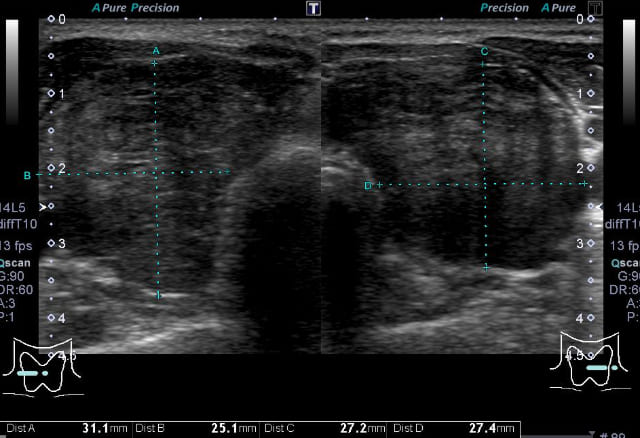

エコー所見では、大きいものでは内部にのう胞性変化を伴っていることが多くあり、この場合は良性であることが多いですが、結節の被膜が不明瞭な部分があったり、結節内部には石灰化を伴うことも多いため、甲状腺乳頭がんとの鑑別が必要なことも多くあります。

②腺腫様甲状腺腫・結節性甲状腺腺腫

甲状腺にできる良性の結節で、機能性(甲状腺ホルモンを出す:プランマー病、中毒性多結節性甲状腺腫)と非機能性に分かれます。

しこりが複数の場合「腺腫様甲状腺腫」、しこりが1つ(またはごく少数)だけの場合「腺腫様結節」と呼ばれます。